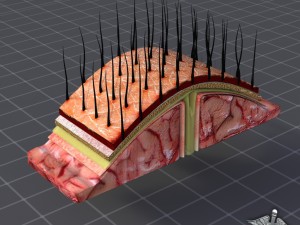

A blend model of brain along with its covering layers (meninges), skull bone and scalp labelled in detail and anatomically precise. The parts depicted are white, gray, pia, arachnoid, dura, bone, skin, fat, aponeurosis, periosteum, falx cerebri and more.

The material is high resolution image textures and normal maps based on non overlapping UVs. The texture and normal maps are packed with the blend file itself.